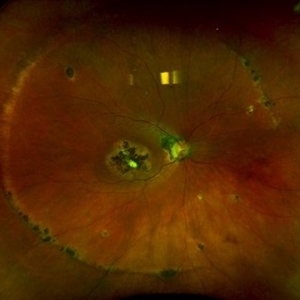

POHS/Schlaegel Lines

POHS/Schlaegel Lines

Sep 19 2024 by Virginia Gebhart

46 year old female with h/o Histoplasmosis. Multiple punched out chorioretinal scars with Schlaegel lines. No evidence of CNV or active inflammation. VA 20/20

Photographer: Virginia Gebhart, Retina Consultants of Carolina

Imaging device: Optos California

Condition/keywords: chorioretinal scar, histoplasmosis, presumed ocular histoplasmosis syndrome (POHS), Schlaegel